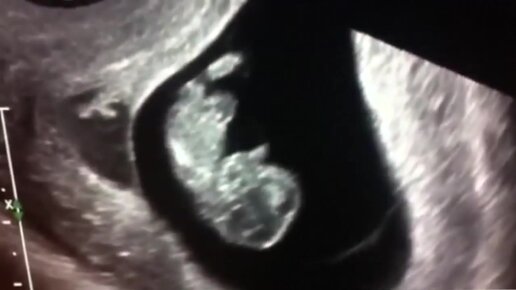

УЗИ на 9 неделе беременности